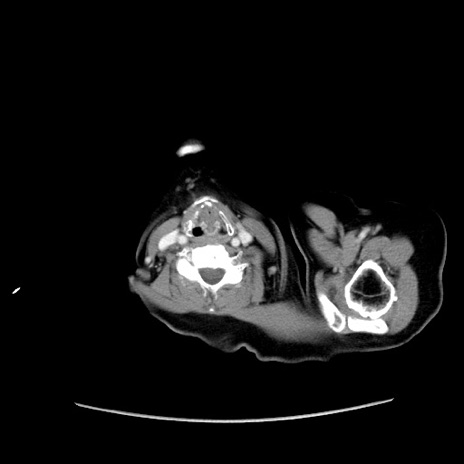

冠状断像